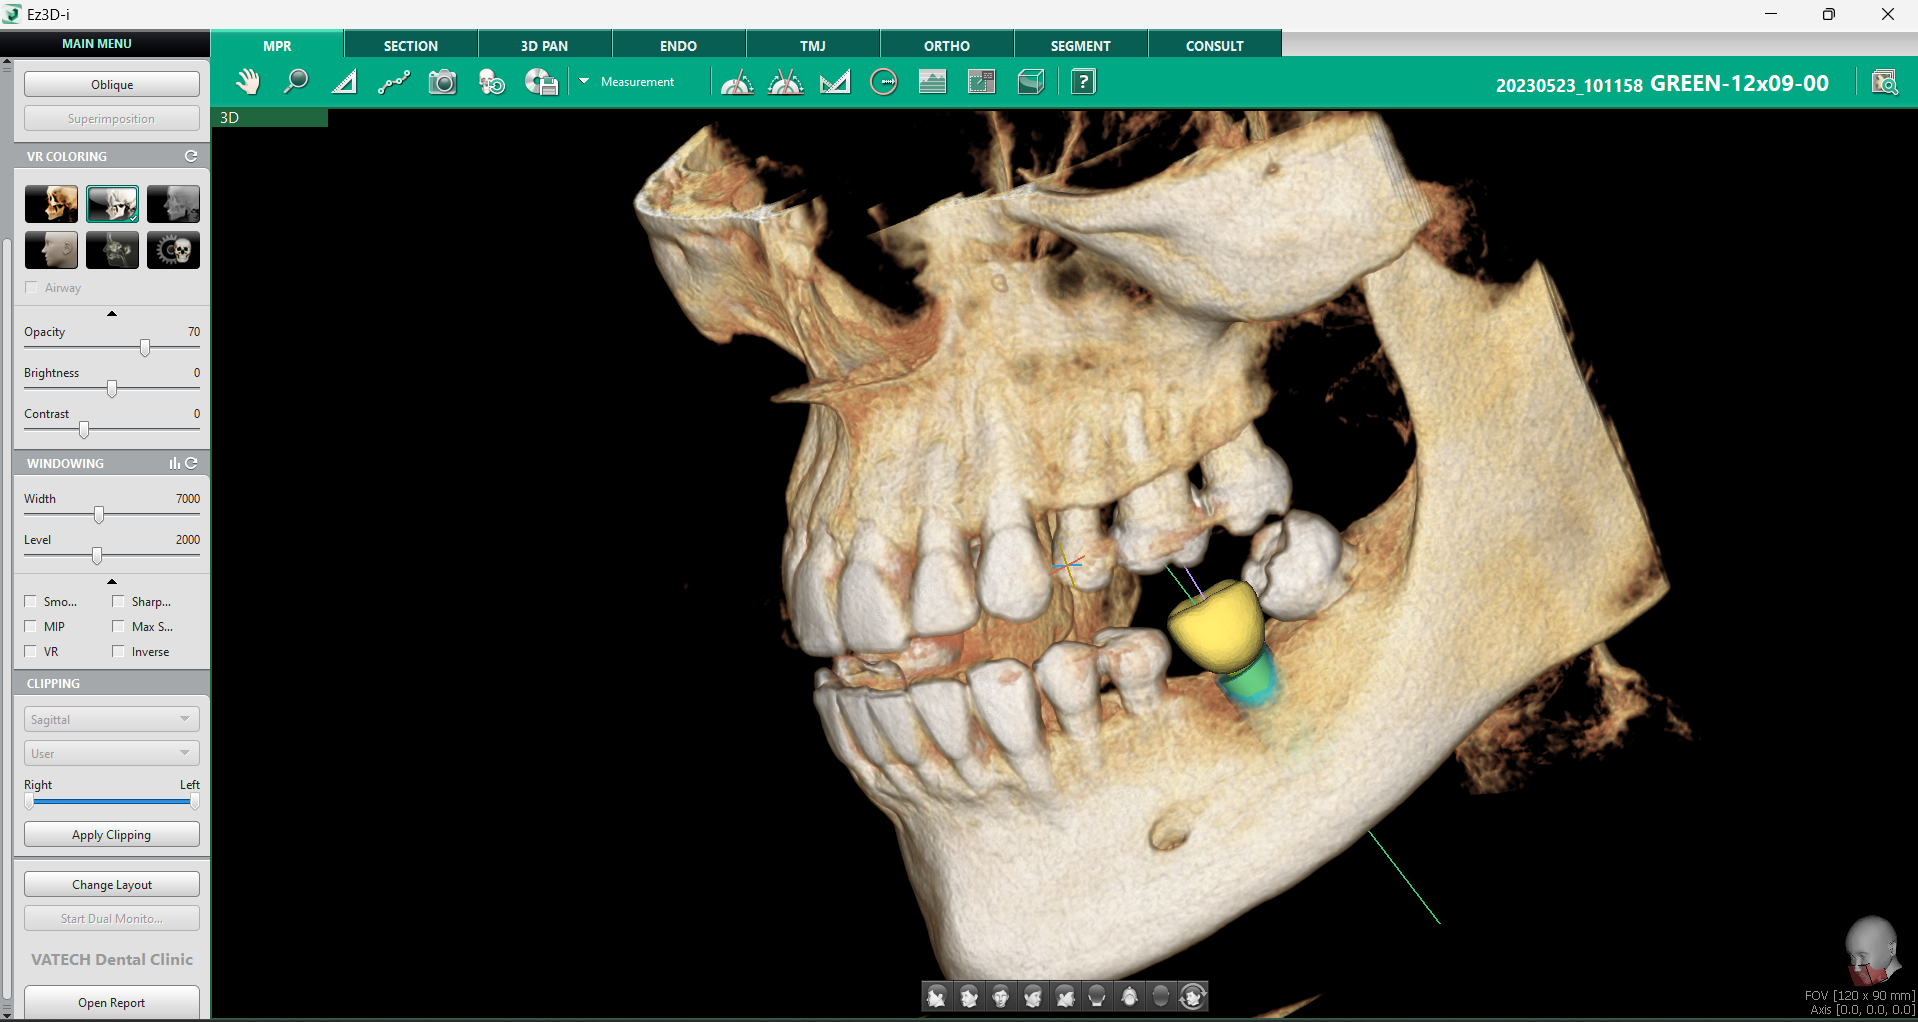

Odată selectată dimensiunea dorită printr-un click stânga, modelul implantului apare instantaneu în imaginea 3D, facilitând plasarea și verificarea sa în timp real.

2. Verificarea poziției implantului

În implantologie, verificarea poziției implantului este esențială pentru succesul procedurii și stabilitatea acestuia pe termen lung. Orice eroare de poziționare poate duce la complicații, de la integrarea deficitară a implantului în os, până la afectarea structurilor anatomice adiacente. Din acest motiv, Ez3D-i oferă o serie de instrumente avansate care permit verificarea multiplă a poziției în timpul plasării implantului, optimizând astfel fiecare etapă a procesului chirurgical.